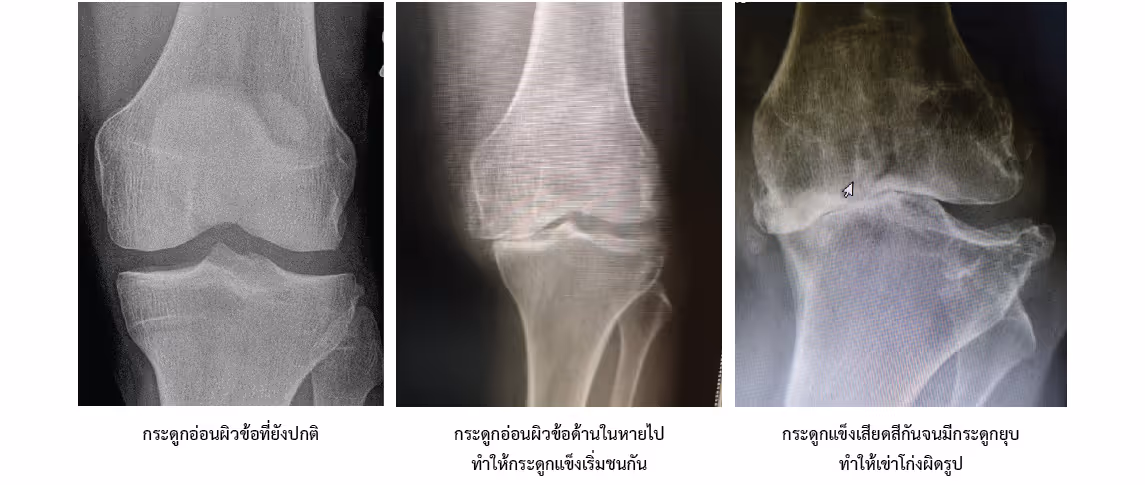

เวลาเกิดข้อเข่าเสื่อมจริง ๆ แล้ว ส่วนที่เสื่อมก็คือ "กระดูกอ่อนผิวข้อ" นี่ล่ะที่เสื่อมไป เมื่อเราอายุมากขึ้น ข้อเข่าผ่านการใช้งานนาน ๆ ทั้งการเดิน การขยับงอเหยียด มีแรงกระแทกลงข้อเข่าซ้ำ ๆ ร่วมกับการเปลี่ยนแปลงภายในกระดูกอ่อนผิวข้อเองที่ความยืดหยุ่นลดลง ทำให้เกิดการแตกสลายหลุดลอกออกของกระดูกอ่อนผิวข้อ เมื่อกระดูกอ่อนผิวข้อหลุดออกไป ชั้นใต้กระดูกอ่อนผิวข้อซึ่งเป็นกระดูกทั่วไปที่มีความแข็ง สาก ไม่ยืดหยุ่น ไม่ได้ถูกออกแบบมาให้รองรับการเคลื่อนไหว เมื่อเกิดการเดิน ขยับ งอเหยียด กระดูกแข็งตรงนี้ก็จะมาเสียดสีกันทำให้เกิดอาการเจ็บปวดเกิดการอักเสบบวมเปรียบเสมือนข้อต่อเครื่องยนต์ที่ไม่มีน้ำมันหล่อลื่น

3. ความผิดรูป (Deformity) ในกรณีที่เป็นรุนแรงมากจนกระดูกอ่อนผิวข้อหายไปหมด เมื่อกระดูกแข็งเสียดสีกันซ้ำนาน ๆ ไป ก็จะทำให้เกิดกระดูกงอก รวมถึงกระดูกบางจุดมีการทรุดตัวลง ทำให้เกิดความผิดรูป ซึ่งมีได้หลายแบบเช่น เข่าโก่ง เข่าฉิ่ง เข่าแอ่น เข่าเหยียดได้ไม่สุด เป็นต้น

โดยปกติการวินิจฉัยจะทำได้โดยการซักประวัติ ตรวจร่างกาย และในบางครั้งอาจจะส่งไปถ่ายภาพ X-ray เพื่อยืนยันการวินิจฉัยรวมถึงประเมินความรุนแรงของข้อเสื่อม

การถ่ายภาพ X-ray ของข้อเข่าจะทำในขณะที่ผู้ป่วยยืนลงน้ำหนัก เพื่อให้มีแรงกดลงไปที่บริเวณผิวข้อ โดยแพทย์จะมุ่งดูบริเวณช่องว่างระหว่างข้อ เนื่องจากกระดูกอ่อนผิวข้อไม่มีส่วนประกอบของ Calcium ในภาพ X-ray เราจึงเห็นเป็นช่องว่างสีดำระหว่างปลายกระดูก ซึ่งหากช่องว่างตรงนี้แคบลง นั่นก็แปลว่ากระดูกอ่อนผิวข้อตรงตำแหน่งนี้ได้เสื่อมสลายออกไป ทำให้กระดูกแข็งๆที่อยู่ข้างใต้มาสัมผัส เสียดสีกัน หากระดับภาวะข้อเสื่อมมีความรุนแรงมาก กระดูกส่วนที่เสียดสีกันก็อาจทรุดตัวลง ทำให้แนวของข้อเข่าผิดรูปได้